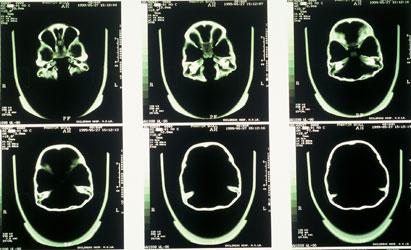

New Orleans. In my home city of New Orleans, Louisiana, Dr. Joseph Smith, a chief radiologist at a childrenhospital, arranged a CAT scan that established none of the Starchildcranial sutures were fused in any way. He ruled out deformity as a result of cranial suture fusion especially the crease in the saggital suture between the expanded parietals. Also, inexplicably, the Starchildinner ears were shown to be on the order of twice normal size and, once again, perfectly symmetrical. Then Carbon 14 analysis showed that death for both skulls had occurred 900 years ago, 40 years.

Denver. The turning point for me came in Denver, Colorado, when a brain specialist made a number of startling discoveries about the Starchildbrain. (This doctor made a specific request that I not name him.) First, its capacity was astounding. Normal human adult craniums contain an average of 1400 cubic centimeters of brain matter. A small-stature adult or a child of about twelve which was the Starchildsize would have a brain in the range of 1200 cc. The Starchild had a brain volume of 1600 cc, which baffled the specialist. Even considering the extreme shallowness of the eye orbits, the missing frontal sinuses, and the expansion of the parietals, he could not account for an increase of fully 1/3 the normal human volume.

He also found that the steep rear angle of the brain pressing down on the foramen magnum the opening where the spine entered the cranium made it unlikely that the cerebellum could have maintained its proper position at the base of the cerebrum. In addition to its steeply canted angle (visible in several of many photos at www.starchildproject.com), the inner support structure of bone flanges (the saggital sulcus and transverse sulcus) was so reduced as to be ineffective as a support mechanism for the cerebellum. The expert could only conclude that the Starchildbrain was made of something denser than normal human brain matter, or it didn't have a cerebellum in the way human cerebellums are understood. Either conclusion was enough to bolster my growing suspicion that the Starchild was not entirely human.